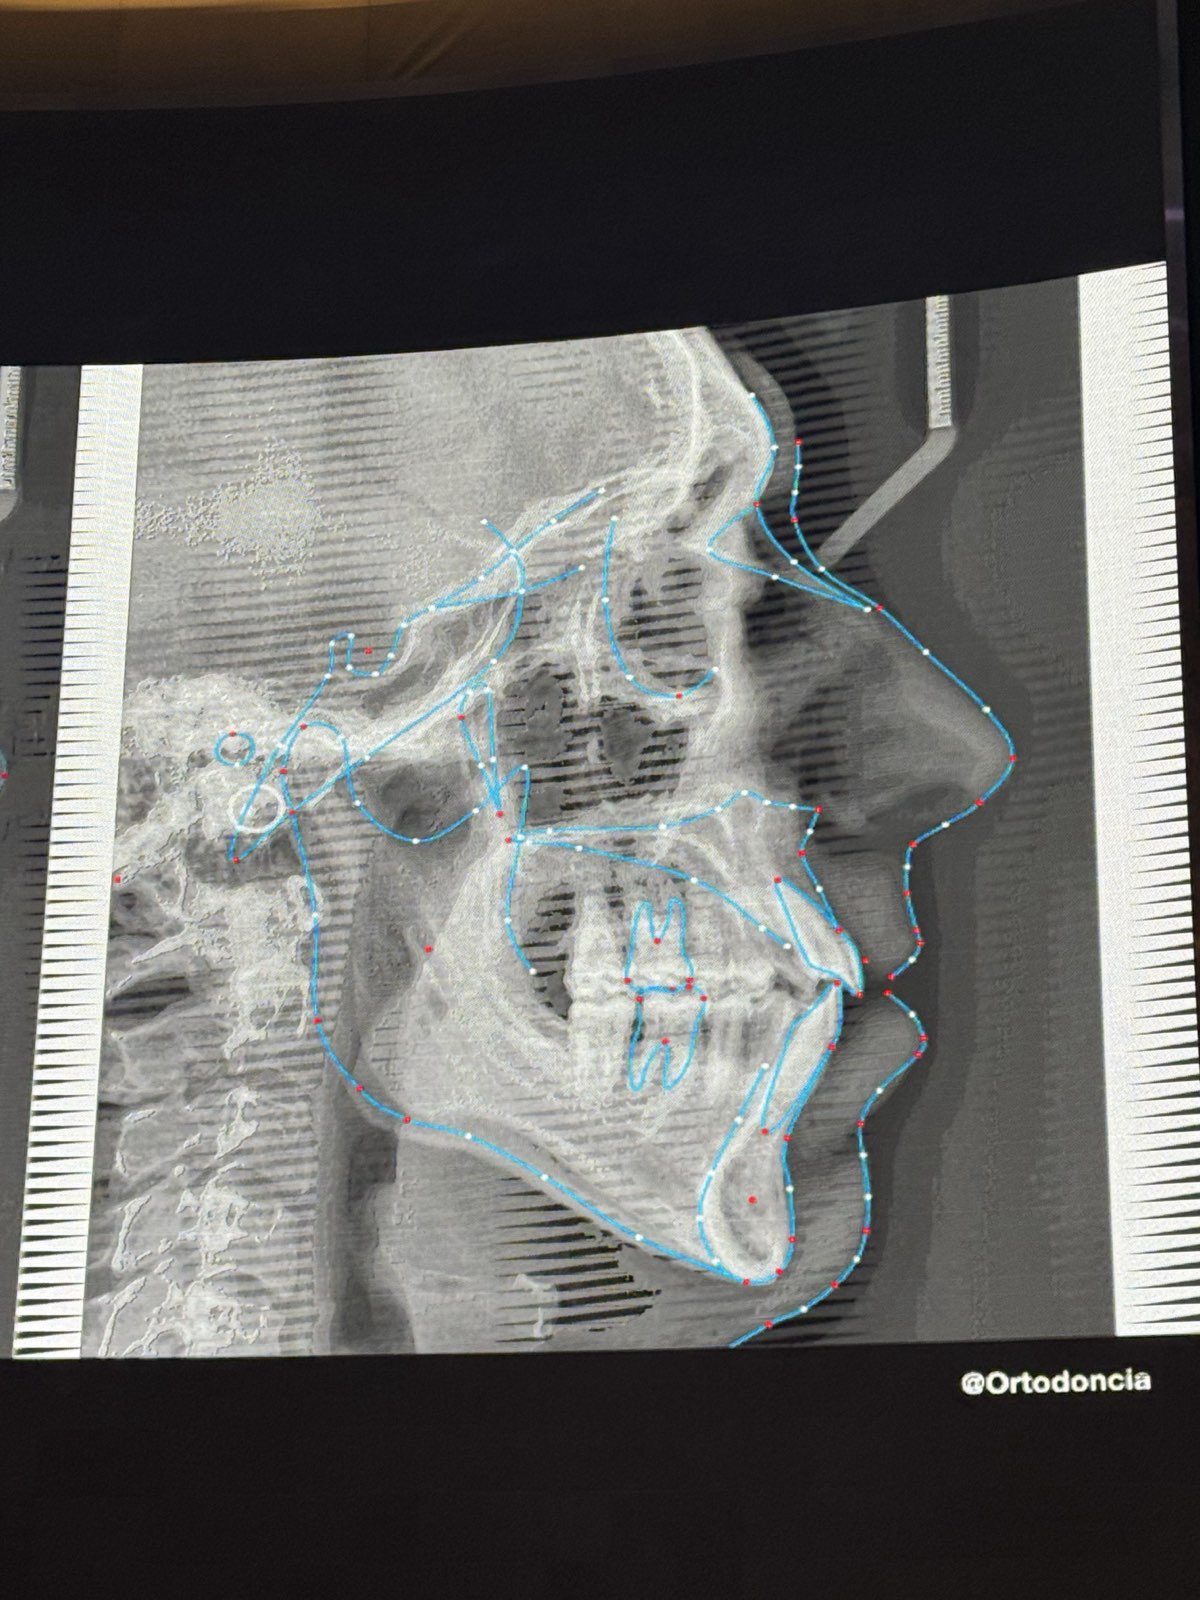

• 症例提示: 重度の顔面形態異常(短顔、下顎後退、短い顔高)を伴うClass II成人患者。手術を拒否。

• 初期診断: Overbite/Overjetの増加、圧下不足(compressions)。Class II症例では横幅の不足(lack of transverse dimension)がよく見られる。

• 治療目標: 拡大(expansion)、トルクコントロール(torque control)、遠心移動(distalization)。

• Occlusal Plane(咬合平面)の回転

• 歯科大学で教わるようなAP(前後的)、横断的、垂直的な平面での歯の移動だけでなく、実際の臨床では「咬合平面の回転」が重要。

• 重度のClass II/Class IIIは、純粋なAP移動ではなく、咬合平面の回転によりClass Iに改善できる。

• 引用: 「私たちは咬合平面を回転させているのです。骨を削ったり、患者の歯根をすべて取り出したりするわけではありません。」

• Class IIエラスティックは「時計回り」に、Class IIIエラスティックは「反時計回り」に歯列を回転させる効果がある。

• 純粋なAP移動だけでなく、咬合平面の回転を考慮することで、困難なケースも解決可能になる。